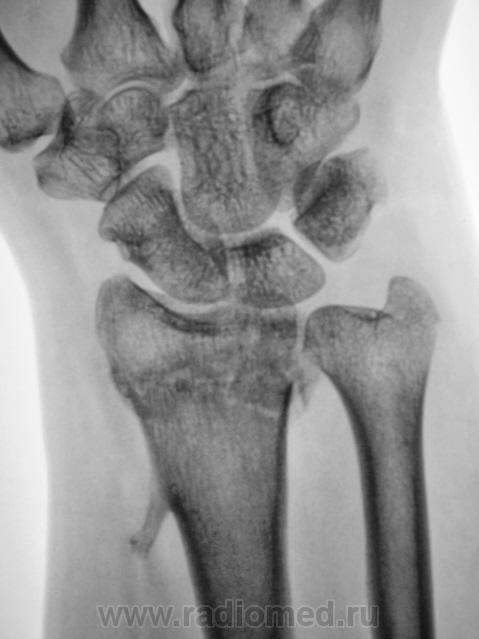

Линия перелома прослеживается,периостальная костная мозоль не выражена,угловое смещение не устранено.

Гипс снят через 1,5 месяца.

по Каплану А.В., - 1979, усредненный срок иммобилизации у взрослых при переломе лучевой кости в типичном месте- 2-4 недели.